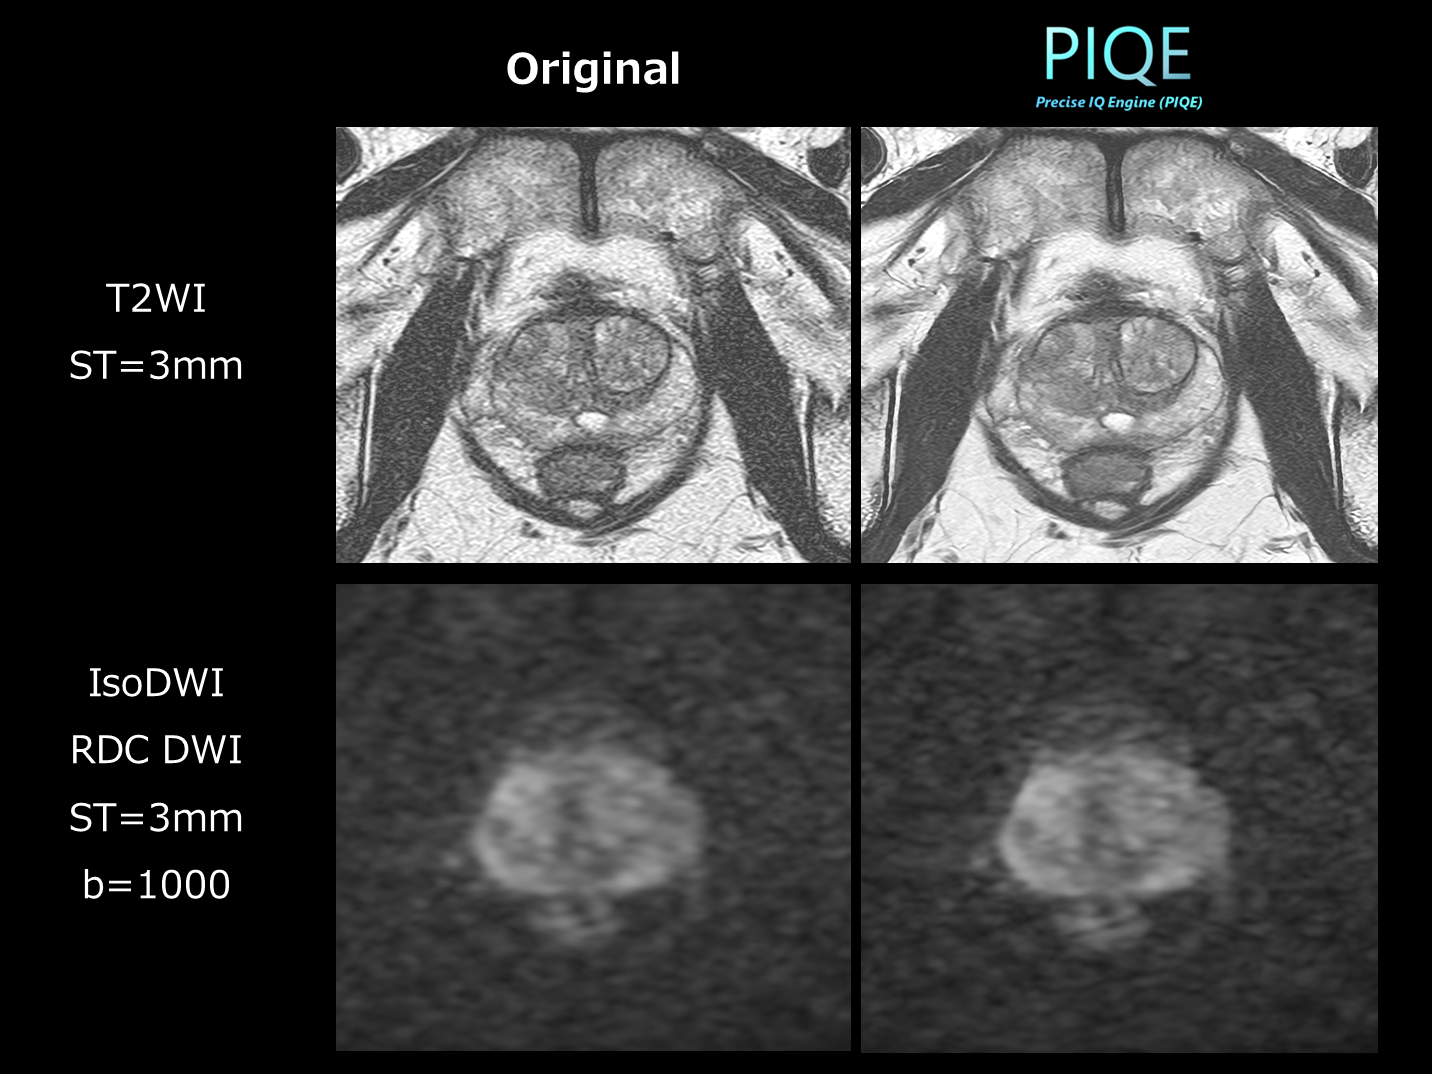

図.4 PI-RADSに準拠した前立腺精査でのPIQE適用例

DLRの恩恵を最も強く実感しているのが、 前立腺領域の検査です(図.4)。従来の1.5T装置では、PI-RADSに準拠したスライス厚3mmでの撮像を行う場合にはハードルが高い印象でしたが、装置更新後はPIQEの活用によりPI-RADSに準拠した条件下でも、十分な画質が得られるようになりました。特に印象的だったのは、もともと3T装置で使用していた高分解能の撮像条件を、1.5T装置で撮像した際の画質です。撮像条件は3Tとほぼ同等であるにもかかわらず、PIQEを適用することで「これなら十分に評価可能」と思えるレベルにまで画質が向上していた点は非常に驚かされました。

当院では、ペースメーカーなどのデバイスを装着されている患者様や、3T装置の検査枠が埋まっている場合などに、1.5T装置で前立腺撮像を行う機会も少なくありません。しかし、PIQEにより3T装置と同程度の条件で撮像しても、同等に診断可能な画像が得られていることは、臨床的にも非常に有用です。